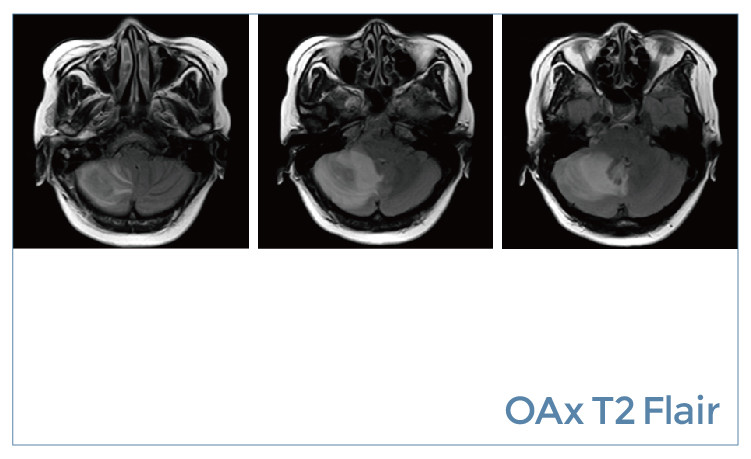

【朗润影像档案】20190802磁共振影像病例结果讨论